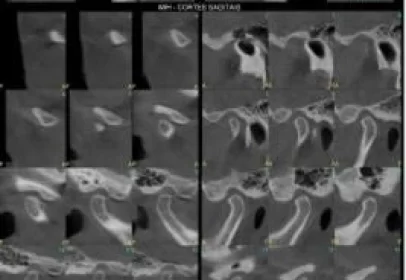

Em nossa clínica é a mais indicada para Endondontia ou quando deseja avaliar nos mínimos detalhes os dentes, como ligamento periodontal, fraturas de raízes, canais laterais, atresia de canais,...